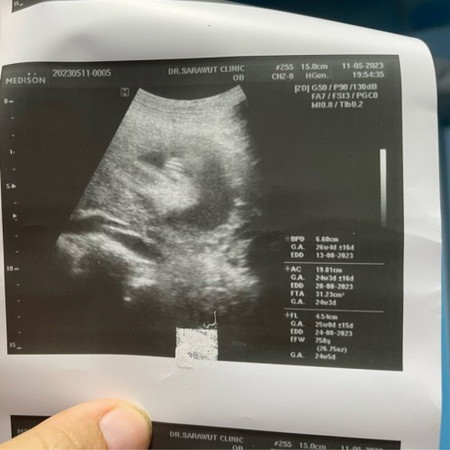

แม่ๆช่วยดูหน่อย

น้องเป็นผู้หญิงไหมคะ🙏

เหมือน ผญ นะคะ น้องไม่มีจู๋โผล่มา

ผญ. ชัดมากเลยค่ะ